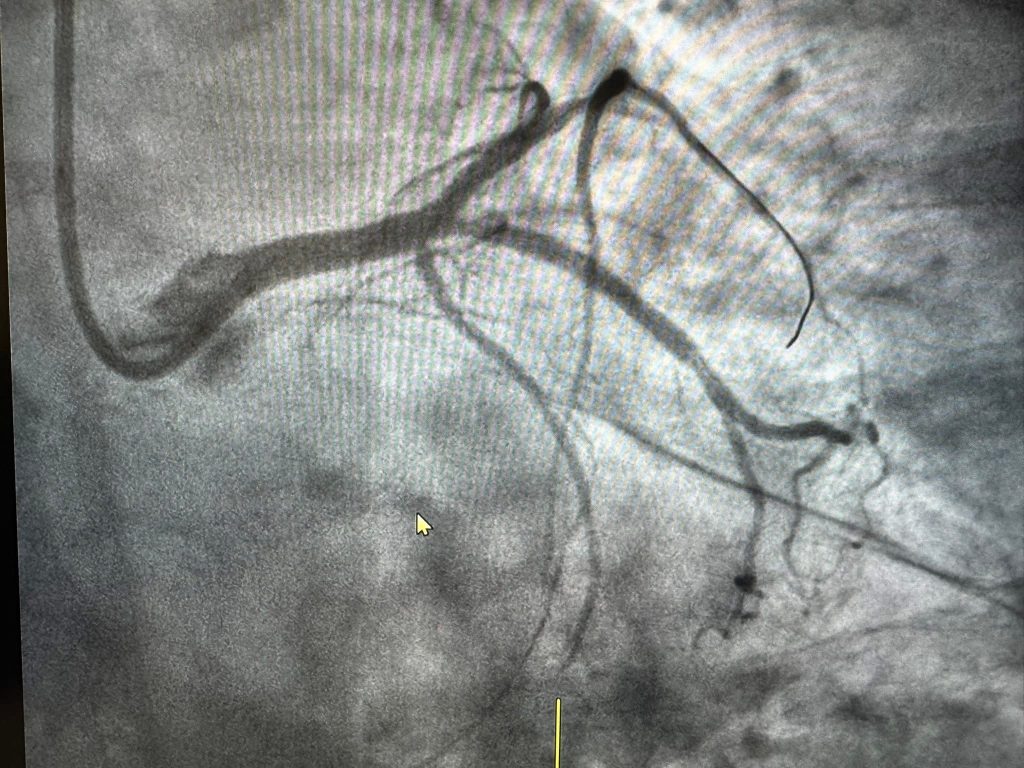

Intervenția a constat în implantarea unui stent și dezobstrucția completă a vasului afectat, procedura fiind realizată cu succes, fără complicații.